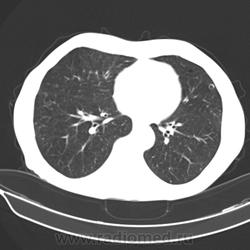

Здравствуйте! Пациент 1951 г. поступил в неврологическое отделение по поводу пареза нижней конечности, жалобы на боли в поясничном отделе позвоночника. Выполнили КТ пояснично-кресцового отдела: кт-картина остеобластических mts в телах позвонков L1-L3, крыле подвздошной кости слева. Клиницисты стали искать первичный очаг. Выполнили КТ органов грудной клетки. По всем легочным полям кольцевидные образования (очаги?) - аспергилёз? Прошу коллег помочь разобраться с заключением.

кистозный паттерн, неравномерно утолщенные стенки, распределение преимущественно периферическое, больше в верхних отделах.

по первому впечатлению - лангергансоклеточный гистиоцитоз (правда возраст не подходит, он чаще у молодых бывает), может сочетаться с раком. Надо копать дальше.

и вообще может быть несколько патологий в одном человеке: cr простаты/моч пузыря с бластическими мтс в позвонки и таз с наличиями в них участков распада и гистиоцитоз (который вероятно тянется с давних времен).

у меня пока связать изменения легких и такие мтс в позвонки с очагом в печени воедино не выходит. похоже разные тут патологии сидят.

Я про легкие и говорил, но больше склоняюсь к кистозным метастазам.

Small Cavitary Lung Lesions

1.Septic emboli

2.Rheumatoid nodules

3.Squamous or transitional cell mets

4.Wegener’s Granulomatosis